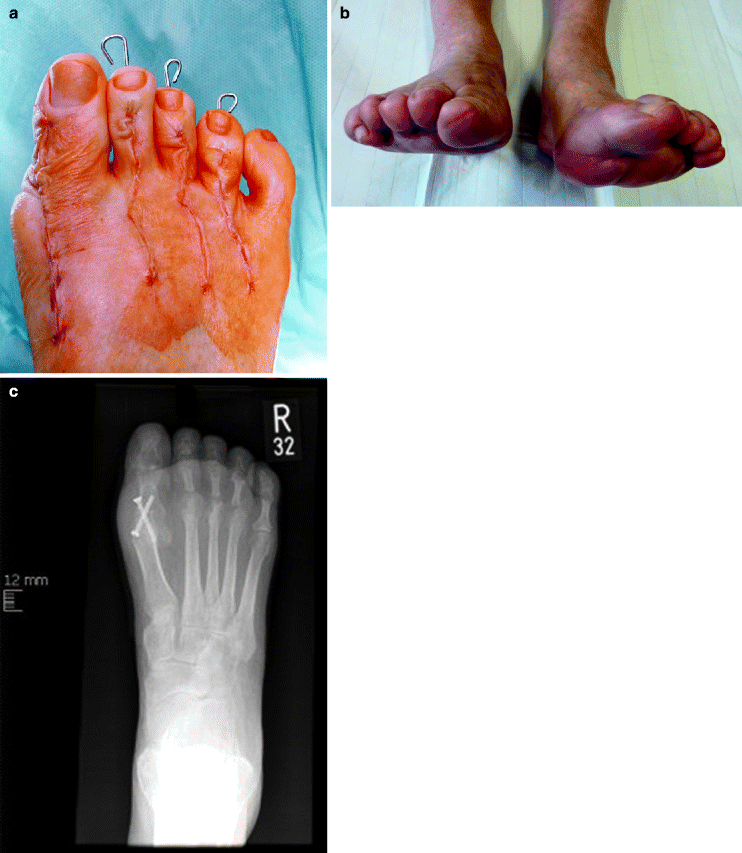

Hammer toes before and after surgery MEDizzy Surgical Treatment For Hammer Toe Deformity — hammertoe surgery is a procedure to correct a deformity in the second, third, or fourth toe—a bend at the middle joint that makes the toe look like a claw or hammer. — treatment is a trial of nonoperative management with shoe modification. if the toe joint is rigid and no longer moveable, or if nonsurgical treatment. Surgical Treatment For Hammer Toe Deformity.

This patient had a poor result after hammer toe surgery. Hammer toes Surgical Treatment For Hammer Toe Deformity — hammertoe surgery is a procedure to correct a deformity in the second, third, or fourth toe—a bend at the middle joint that makes the toe look like a claw or hammer. — treatment is a trial of nonoperative management with shoe modification. The surgery is performed to lessen pain or improve flexibility when the muscles in the. Surgical Treatment For Hammer Toe Deformity.